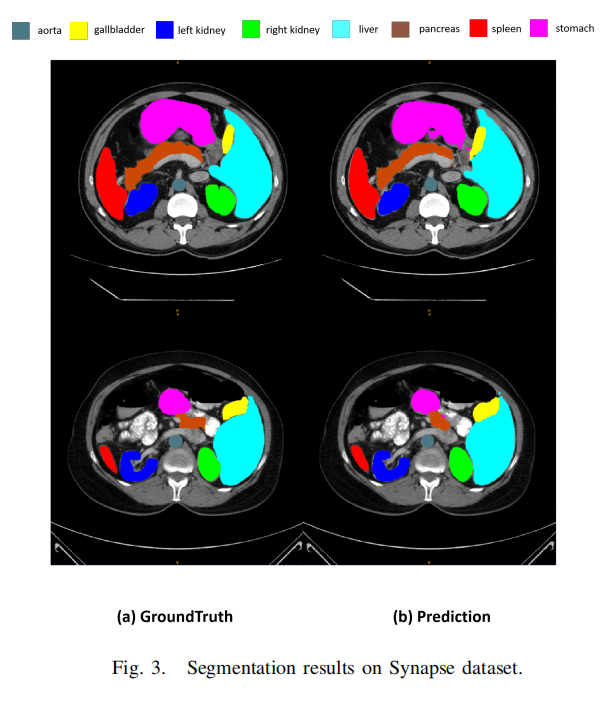

本文使用Synapse数据集进行评估,这是MICCAI 2015多图谱腹部标记挑战的一个公开可用的多器官分割数据集。它包括30个腹部CT扫描。根据之前的工作,总共使用18个案例进行训练,12个案例用于测试。本文以Dice相似系数(DSC)和95% Hausdorff距离(HD95)的指标报告在8个腹部器官(即主动脉、胆囊、脾脏、左肾、右肾、肝脏、胰腺、胃)上的结果。

表I报告了实验结果,并与其他最先进的方法进行了比较。本文提出的方法实现了79.45%的DSC和35.35mm的HD95分数。本文还观察到可学习权重参数的值为0.44。本文的方法在超过大多数最先进方法的同时取得了竞争性的得分。

图3展示了一些分割结果。然而,集成CNN编码器和可学习权重参数的设计可以进行修改,以分析和评估所提出方法的性能。本文相信利用Transformer或其他有效的网络设计将会获得更高的性能。在未来,本文将探索更先进的设计选择,以达到最佳结果。